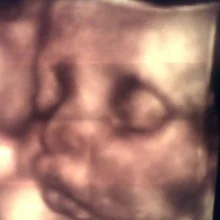

Sobre Control de Embarazo

Seguimiento prenatal